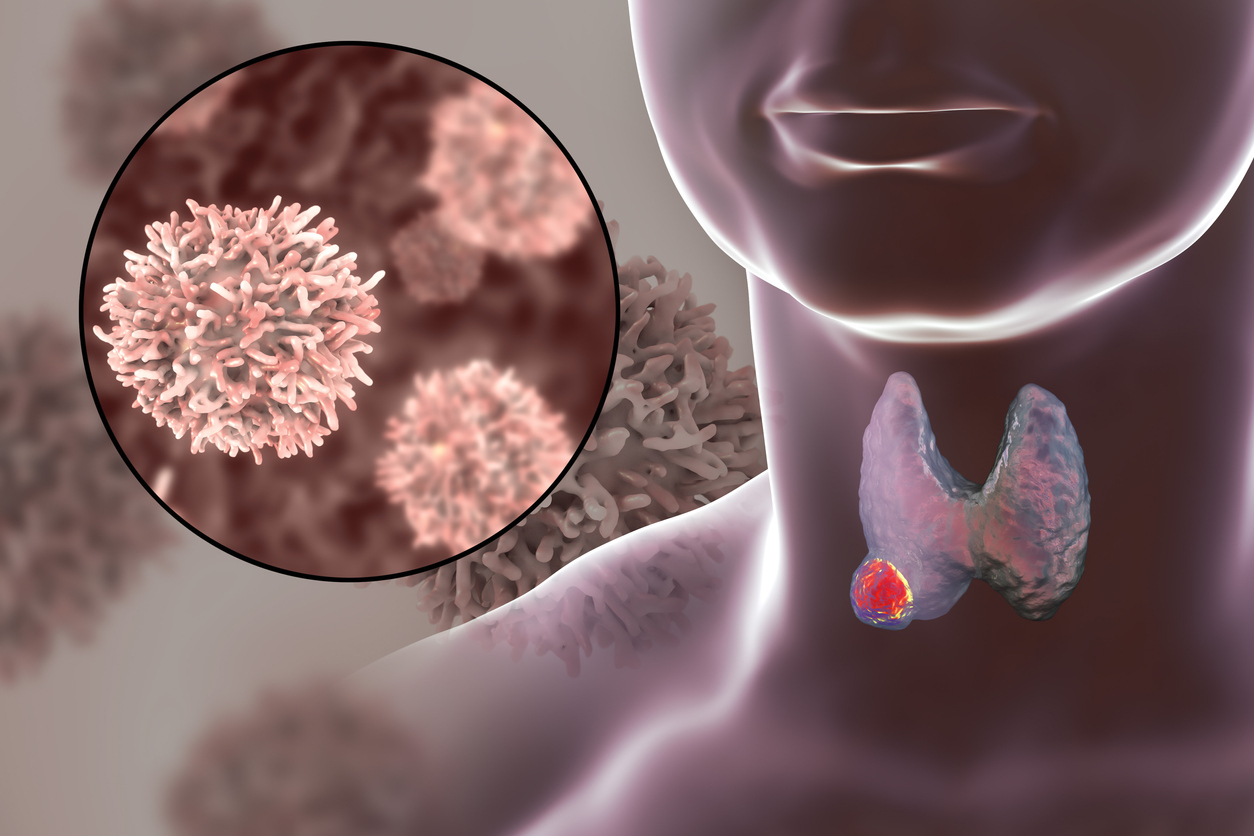

Ο θυρεοειδής αδένας βρίσκεται στον λαιμό, κάτω από τον λάρυγγα (μήλο του Αδάμ στους άνδρες). Αποτελείται από δύο λοβούς εκατέρωθεν του σωλήνα, ενώνονται στο μπροστινό του μέρος με μια “γέφυρα”. Ο θυρεοειδής αδένας εκκρίνει ορμόνες που ρυθμίζουν πολλές μεταβολικές διεργασίες, όπως η σωματική ανάπτυξη και η ενεργειακή δαπάνη του οργανισμού.

Ο καρκίνος θυρεοειδούς επηρεάζει περίπου 1 στους 1.000 ανθρώπους με τις γυναίκες να είναι ελαφρώς πιο επιρρεπείς από τους άνδρες.